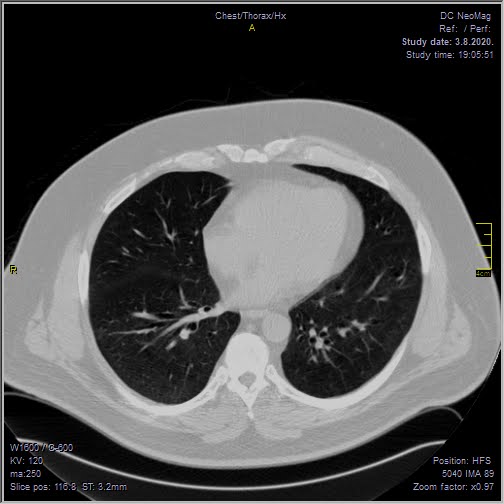

Foto: Privatna arhiva Foto: Privatna arhiva Foto: Privatna arhiva Radiolog pokazao snimak pluća i mozga 3 meseca posle kovida autor: Božica Luković Zdravlje 09. okt. 2020. 12:26 0 Podeli vest: Radiolog Aleksandar Ivković na svom blogu pruža naučni uvid u sve pojave koje je sa sobom donela pandemija koronavirusa. Rešio je da podeli kakvo je stanje jednog pacijenta tri meseca nakon što je preležao opaki virus. Podeli vest: Oglas Lekari i dalje ne znaju sa sigurnošću kakve sve posledice kovid 19 ostavlja po organizam. Postoje čak osobe koje više meseci pate od bolesti koju izaziva novi koronavirus, a mnogi prijavljuju i brojne tegobe koje ih muče i nakon negativnog testa.Niški radiolog, čije smo tekstove prenosili i ranije, ovog puta je odlučio da podeli snimke pluća i mozga svog pacijenta, koji je preležao virus pre tri meseca.Objavu sa bloga Aleksandra Ivkovića "Ljudi i ostale laži", prenosimo u celosti."Obećao sam da ću preneti kakvo je stanje pacijenata nakon kontrola. Ovde se radi o pacijentu koji je u grupi 50 - 60 godina, muškog pola, imao teži oblik kovida, nije bio na respiratoru, samo na kiseoniku.Prvi put kada sam ga pregledao bio je početak jula. Obostrana pneumonija. Foto: Aleksandar Ivković | Foto: Aleksandar Ivković Ime sam uklonio, datum se vidi, kao i ime ustanove. Ove bele fleke u plućima, koje kada se malo uveća, liče na mutno staklo, su ustvari žarišta pneumonije. Foto: Aleksandar Ivković | Foto: Aleksandar Ivković Kada bi ove bele "fleke" počele da se šire ka sredini, ka srcu, to bi značilo da se bolest širi i da se razvija citokinska oluja. Nije došlo do toga.Pacijent je došao na kontrolu nakon mesec dana. Žali se samo za zamaranje. Nema tegobe, samo želida vidi kakvo je stanje pluća. Foto: Aleksandar Ivković | Foto: Aleksandar Ivković Evidentno više nema onih zona zapaljenja. Bronhi su lako zapaljeni, mogu da se uoče mesta na kojima je bilo zapaljenje. Foto: Aleksandar Ivković | Foto: Aleksandar Ivković Ako se zagleda malo bolje prisutne su zone oštećenja alveola ali to ne spada u neki nalaz koji je zabrinjavajući.Skoro dva meseca kasnije, ponovo dolazi na pregled. Ovaj put nisu pluća u pitanju. Žali se da je konfuzan, da ne može da se seti nekih reči, da ne može da završi rečenice, da ima rupe u pamćenju.Urađen je MR pregled mozga. Foto: Aleksandar Ivković | Foto: Aleksandar Ivković Jedna ishemijska lezija, nekoliko mikroishemijskih lezija i atrofija mozga.Takav nalaz se uklapa u tegobe koje je pacijent opisao. Takođe se uklapa u ono što opisuju drugi da vide kod svojih pacijenata.Za one koji nisu shvatili još uvek - kovid 19 je opasna bolest. Od nje se umire, ostaju posledice. Nikako nije za igranje.Nikako nije ni za namerno zaražavanje, kako su neki pozivali", napisao je radiolog.***Bonus video:https://www.youtube.com/watch?v=PtivsKpglHYPratite nas i na društvenim mrežama:FacebookTwitterInstagram Srpski radiolog: 5 zabluda o asimptomatskim pacijentima Zdravlje 0 Ispovest srpskog radiologa: Golgota korone u sedam dana Zdravlje 0 Profesor Vujčić raskrinkao srpske teorije zavere o koroni Zdravlje 0 aleksandar ivković posledice koronavirusa Pratite nas na društvenim mrežama: Koje je tvoje mišljenje o ovoj temi? Učestvuj u diskusiji ili pročitaj komentare Budite prvi koji će ostaviti komentar Pošalji komentar Pročitaj komentare (0)